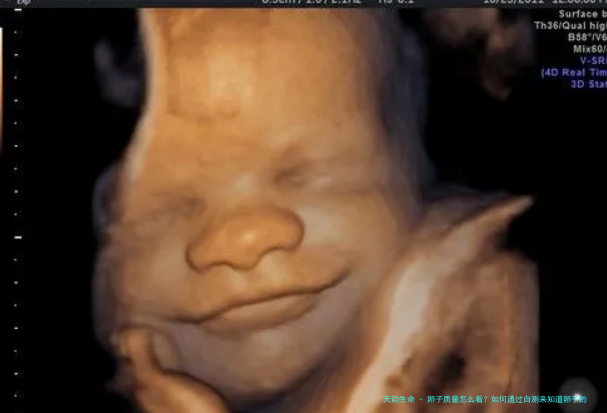

3. 超声波检查

通过阴超波检查,医生可以直接察看卵巢中的卵泡生长状况。卵泡的大小、数目以及样子可以反响卵子质量。通常来讲,成熟的卵泡直径在18-24毫米之间,很小或过大的卵泡均可能导致卵子质量减少。